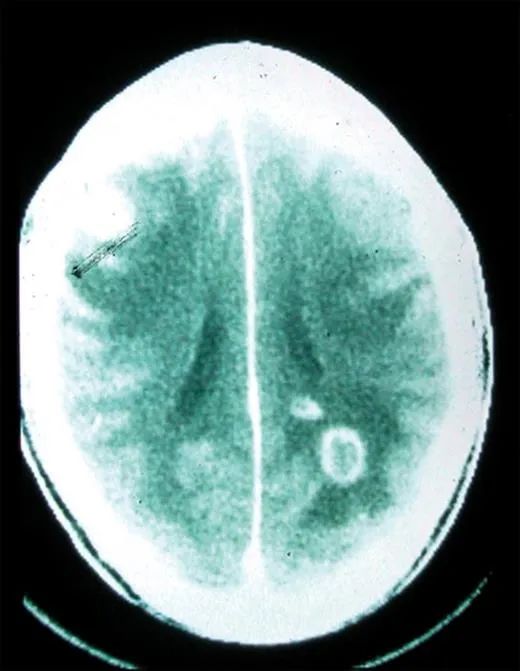

人體內原本存在一些屏障,將人體重要部位與身體其他部分的內環境分割開來,防止病原體的入侵,但弓形蟲卻能夠跨越這些屏障。例如,它們就能跨越血胎屏障,這就是為何如果孕婦感染了弓形蟲,可能對胎兒造成嚴重的影響,嚴重時甚至可能導致流產;它們也能跨越血腦屏障,並引起各種中樞神經病症,比如癲癇等。當然,它們也能跨越血睾屏障,對男性的生殖系統產生影響。

弓形蟲感染人類大腦(圖片來源:Sullivan & Jeffers, 2012)